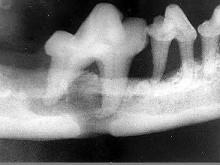

颌面外伤患者,咬合错乱,下唇麻木张口受限,经X 线检查如图。应该为 ( )

- A.上颌骨骨折

- B.颧弓骨折

- C.牙槽突骨折

- D.下颌骨骨折

- E.颧骨骨折

D